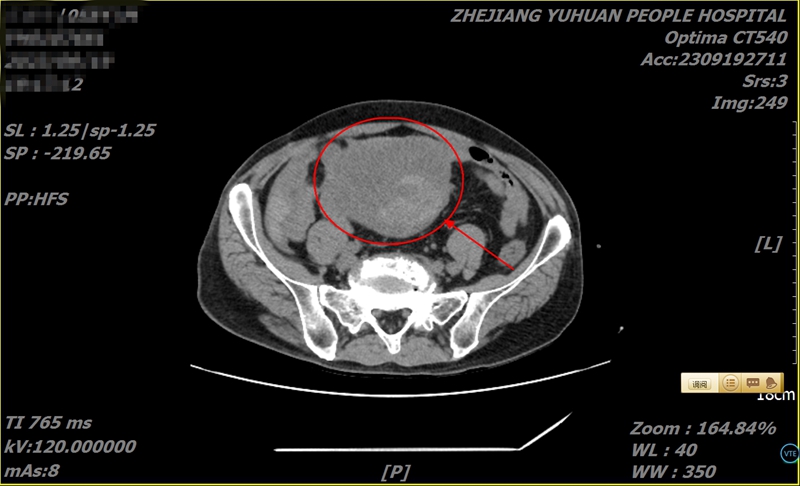

果不其然,杨叔一来到玉环市人民医院,外科副主任医师张富火速为其检查,竟发现小肠上有一橄榄球大小的巨型肿瘤,且伴有肠梗阻,盆腔积液、积血!

“赶紧通知手术室急诊手术!”张富凭借经验判断,这是罕见的小肠间质瘤,且已经破裂出血,手术时间不容延误。

危急时刻,完善术前准备后,杨叔转瞬被送往手术间,张富与医生周方建二人紧急为其手术。术中发现,肿瘤最长直径长达12厘米,瘤体上方一血管破裂,腹腔积血已达250毫升。